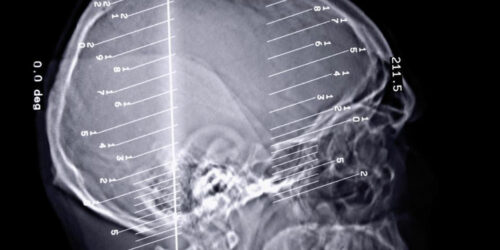

The human body can perform all its functions seamlessly when every organ of the body works in unison to perform the task. A slight change in the functions of the organ can disrupt the entire functioning of the body. Epilepsy seizures are a kind of disorder that occurs when we there is a problem in our brain’s electrical system.

Almost any disorder that ails us can be treated. Being an earthling in the 21st century comes with its added benefits. Anything that affects us or interferes with the normal functioning of our bodies can be treated effectively. They don’t survive an onslaught of effective medications and succumb to it finally and thus, you can say “good riddance to bad rubbish.” Epilepsy is a neurological condition that causes a sudden surge of electrical impulses in the brain, which cause epilepsy seizures symptoms to surface.

Epilepsy is a dreaded disorder, especially since it is connected to the dysfunctioning of the brain. The brain plays a pivotal role in the functioning of the human body and any kind of issue can lead to severe complications. The disorder is related to the dysfunctioning of the central nervous system in the brain.

Epilepsy is a disorder of the brain that has consequences wherein a person suffers from seizures and periods of unusual behavior. It is particularly the disruption of the functioning of the nerve cell activity in the brain and can also lead to a loss of consciousness for long periods of time.